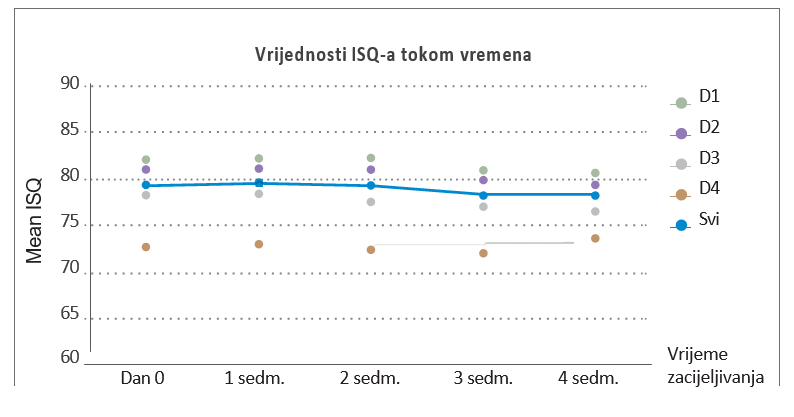

- Kako bi se minimalizirao pad ISQ-a (Koeficijenta stabilnosti implantata) nakon ugradnje i smanjilo trajanje tog pada

Kod četrnaest pacijenata izvršena je ugradnja 40 AnyRidge implantata: među njima, 39 implantata s ISQ vrijednošću > 70 nakon 3 sedmice zacjeljivanja opterećeno je privremenom restauracijom.

Vrijednosti ISQ-a su bile stabilne za sve implantate.Konačna protetska restauracija je postvaljena nakon devet sedmica kada su ISQ vrijednosti implantata u području s transplantatom bile približno 70. Uz dopuštenje Dr. Chang-Hun Han